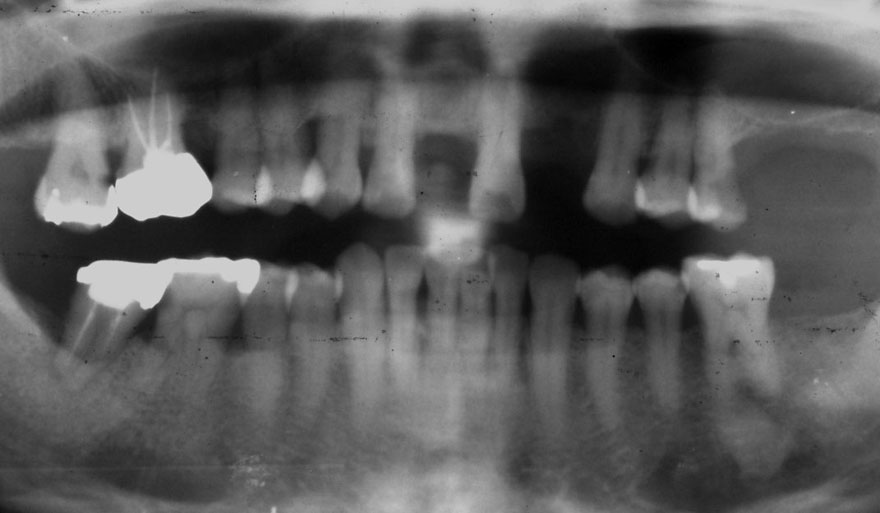

開始年齢 40代

初診時 40歳 女性 平均歯槽骨喪失量:3.14mm

32年後 72歳

平均歯槽骨喪失量:3.22mm

32年間喪失量:-0.08mm

年間喪失速度:-0.002mm

(ケア頻度:1.86ヵ月ごと)